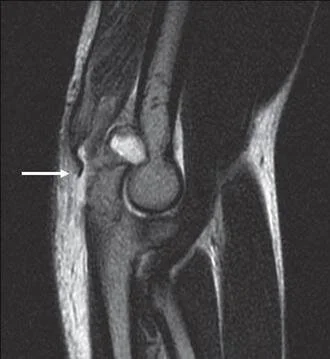

MRI showing the triceps ruptureJ Hand Surg Eur Vol. 2012 Jan;37(1):71-2.

MRI showing the triceps rupture

J Hand Surg Eur Vol. 2012 Jan;37(1):71-2.